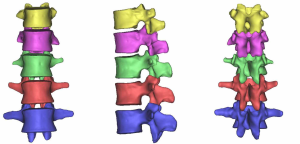

At the end of the tomographic image processing, three-dimensional surface model of the spine and pelvis was reconstructed using the three-dimensional calculation function of the software to generate independent skeletal models of each vertebral body and sacrum in order to clearly and directly reproduce the three-dimensional morphology of the bone structure. The image from the three-dimensional reconstruction could be demonstrated by rotation in all directions and translation. It was also possible to hide, delete, add, and merge the components as needed in this model to obtain different looks and effects (Figure 6).

The bone model reconstructed by the above method only contained three-dimensional surface elements with entities. The data of each bone model automatically included the position coordinates in the overall coordinate system of the vertebral body, and its information was exported through a point cloud and then imported into the reverse engineering software SolidWorks to further establish the entity model. SolidWorks preserved the original spatial relationship of each vertebral body without loss and directly formed the assembly.

The three-dimensional entity model of T11–L3 and the screw-rod system were constructed using SolidWorks (Figures 7-9).